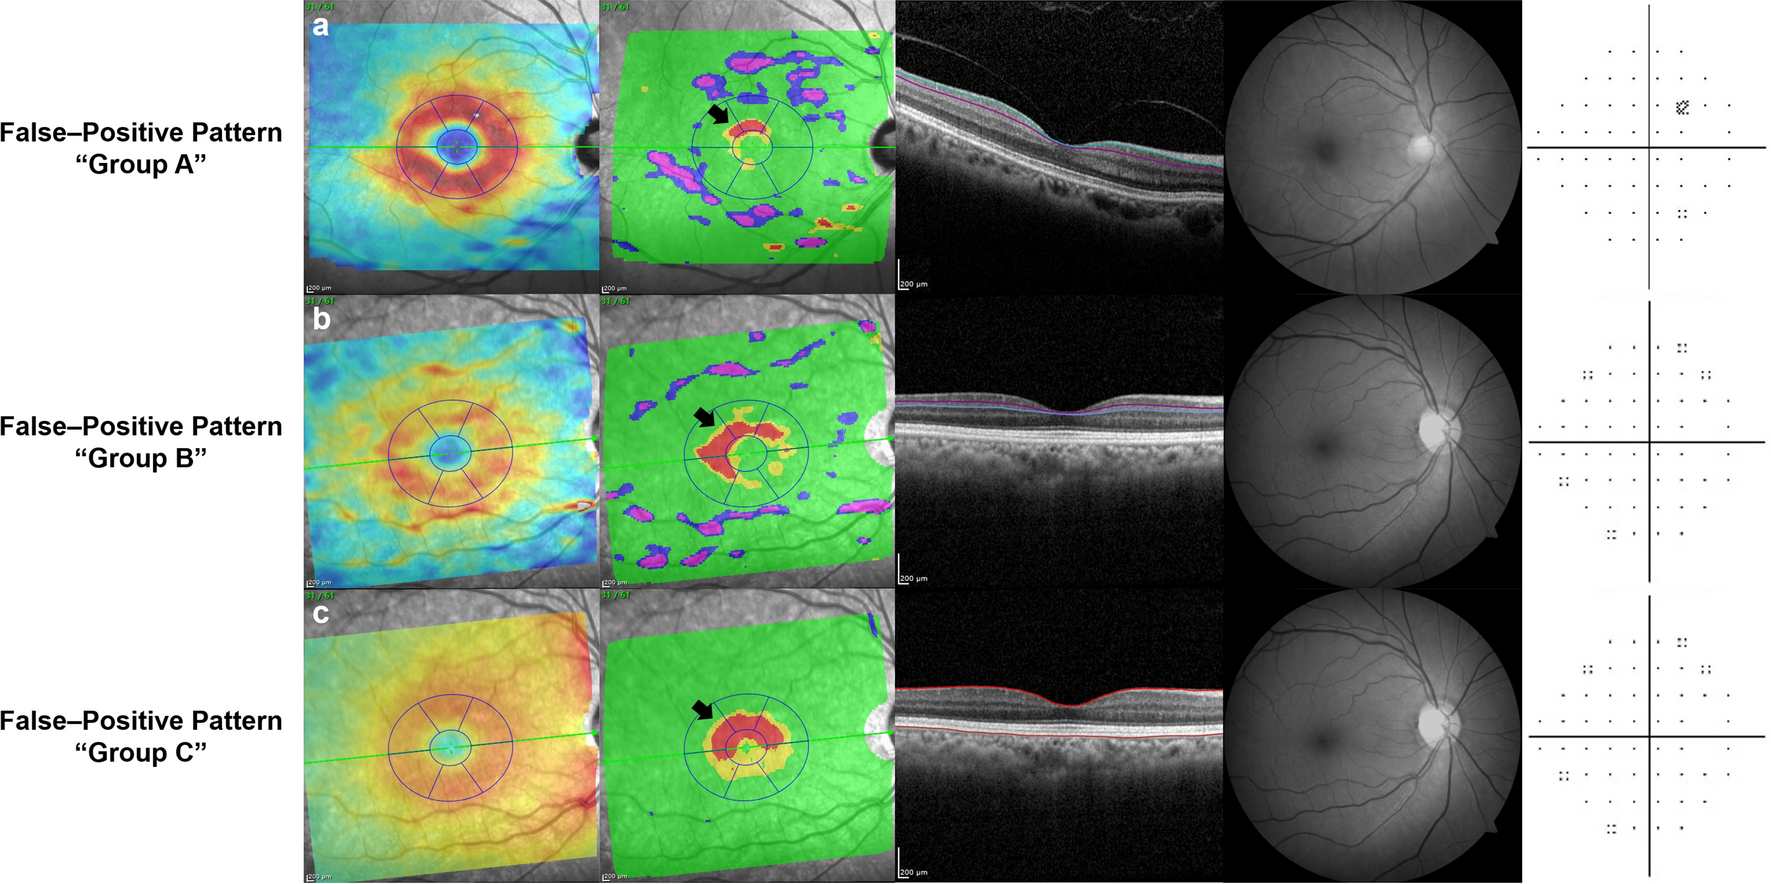

Figure 3

False-positive patterns on deviation maps of segmented macular layers on Spectralis OCT. Each labeled row (a–c), from left to right, consists of a thickness map, a deviation map, a corresponding B-scan with colored lines demarcating the segmented layer, red-free retinal nerve fiber layer (RNFL) photography and Humphrey (Carl Zeiss Meditec, Dublin, CA, USA) C24–2 visual field. (a) Healthy eye of 58-year-old female with pattern group A (island shape circumpassing less than 180° in area) on ganglion cell layer (GCL) deviation map. (b) Healthy eye of 66-year-old female with pattern group B (hook shape circumpassing more than 180° but less than 360° in area) on inner plexiform layer (IPL) deviation map. (c) Healthy eye of 66-year-old female with pattern group C (donut shape around inner annulus, circumpassing 360° in area) on retinal layer deviation map.